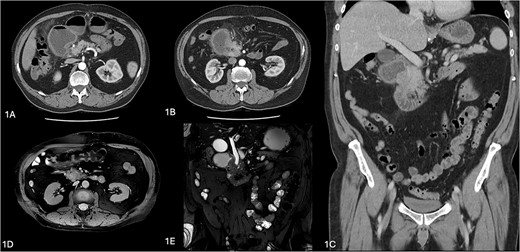

The patient was admitted for further work-up. A computed tomography (CT) scan revealed a duodenal outlet obstruction with a transition point at the level of the pancreatic head with periduodenal fat stranding and duodenal wall thickening, with the impression of enhancing pancreatic tissue lateral to the duodenum at this site (Fig. 1). Magnetic resonance cholangiopancreatography (MRCP) suggested an abrupt transition in the caliber of the second part of the duodenum by an obstructive periampullary lesion, through which a dilated extrahepatic bile duct (9 mm) passed through (Fig. 1). The pancreatic duct size was normal with no surrounding lymph node enlargement or vascular encasement by the pancreatic parenchyma. His liver enzymes and serum tumor markers (carbohydrate antigen 19–9 (CA19–9), carcinoembryonic antigen, and alpha-feto protein) were unremarkable. His serum lipase level was 171 U/l. An endoscopic ultrasound (EUS) of the upper gastrointestinal tract was performed to assess the obstructive periampullary lesion (Supplementary Video 1).

Radiological images of annular pancreas. (A–C) Computerized tomography images showing duodenal obstruction with a transition point at level of pancreatic head with periduodenal fat stranding and duodenal wall thickening, with impression of enhancing pancreatic tissue lateral to duodenum at this site. (C, D) Magnetic resonance cholngiopancreatography images showing an abrupt transition in the caliber of the second part of the duodenum by an obstructive periampullary lesion, the annular pancreas.

An annular pancreas was suggested by the CT and MRCP, and the diagnosis of a complete annular pancreas was confirmed on EUS. Consideration was given for malignancy of the pancreatic head, but this was ruled out with normal tumor markers and biochemical markers and EUS findings (no discrete pancreatic mass or lesion otherwise).